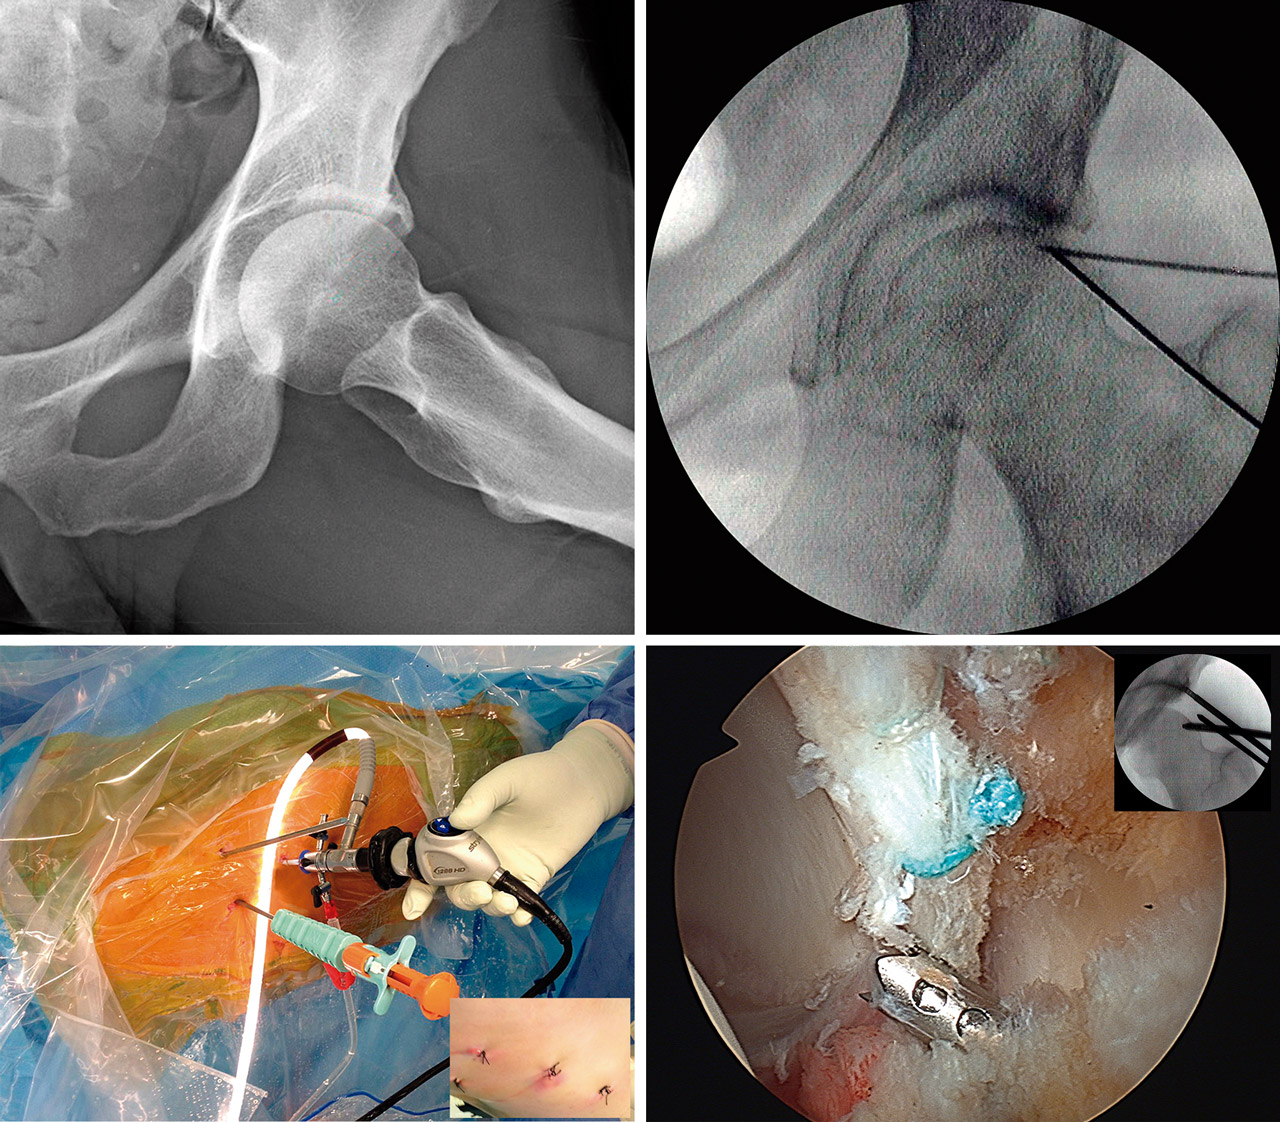

Aunque, como hemos descrito, es posible realizar un abordaje primario central en estos casos, personalmente optamos casi siempre por realizar una técnica de “fuera-dentro” desde el espacio precapsular, abordando en primer lugar el compartimento periférico. Ello nos permite en primer lugar identificar el obstáculo óseo y la lesión labral, practicar el desbridamiento y la retirada de dicho obstáculo, abordando seguida y más cómodamente el CC tras instaurar, en ese momento y no antes, la tracción(8). Si se demuestra necesario, iniciamos también la acetabuloplastia de resección antes de entrar al CC. Con todo ello disminuimos el tiempo total de tracción y el riesgo de lesiones condrales y labrales añadidas.

Abordaje y portales

Como hemos señalado, realizamos el abordaje de la articulación desde el espacio precapsular, abordando en primer lugar el compartimento periférico según la técnica de “fuera-dentro” descrita por Horisberger(7)(8), popularizada en nuestro entorno por Margalet(12). Iniciamos la artroscopia con la óptica de 30° a través de un portal anterolateral (PAL). Dicho portal es análogo, en su ubicación, al de la técnica “dentro-fuera” descrita por Byrd en posición supina(5). Únicamente se aleja 4 cm del borde anterior del trocánter en dirección a la línea media del muslo de forma análoga a la técnica de abordaje desde el compartimento periférico, descrita por Dienst también sin tracción y en DS(6). Se permite así una oblicuidad de unos 10° de arriba hacia abajo que facilita el abordaje del espacio precapsular (Vídeo).

Aunque la técnica se puede realizar solamente mediante 2 portales(4), preferimos emplear 2 portales auxiliares de trabajo (3 en total), uno anteromedial más proximal (PAMP) y otro anteromedial distal (PAMD), similar al anteromedial modificado descrito por Matsuda(4), pero realizado bajo visión directa. El primero de estos 2 portales se establece bajo control radioscópico y permite realizar el desbridamiento del espacio precapsular, la capsulotomía, la desinserción lateromedial del LIF y la resección del PINCER en la zona anterior y superior (Vídeo).

El segundo portal auxiliar (PAMD) lo practicamos, como hemos señalado, bajo la visión intraarticular de la inserción de un catéter de abordaje, de forma que, permitiendo una correcta triangulación, se consiga el mejor ángulo y posición para la inserción de los anclajes, completar la acetabuloplastia en la zona posterior y, finalmente, suturar la cápsula de los casos indicados(13)(14).

Para llevar a cabo la resección de las formas con exceso de cobertura, seguimos los conceptos de planificación propuestos por Matsuda(15). Así, dibujamos sobre la pantalla del intensificador el patrón de la zona de resección en la proyección anteroposterior (AP), como propugna Matsuda(15), pero también lo hacemos en la axial. Ello nos permite definir mejor la resección anteromedial y la superolateral. Iniciamos la resección de la zona superior y anterior de más fácil acceso, lo que además nos permitirá ir ampliando la resección. Dirigimos esta primero hacia la zona más anterior y medial, y después a la más lateral y posterior. Nos guiaremos en nuestra resección secuencial por las marcas realizadas sobre el intensificador hasta comprobar la normalización del ángulo de cobertura (zona superolateral) y conseguir la neutralización del signo de la pared posterior. Artroscópicamente, comprobamos la desaparición de los signos dinámicos de choque. La resección media realizada en estos casos es de unos 10 mm, como se ha publicado(15). Durante toda esta parte del procedimiento, mantendremos una tracción mínima, siendo suficiente evitar lesionar el cartílago de la cabeza femoral durante la acetabuloplastia de resección del PINCER. Una vez completada, aumentaremos la tracción e iniciaremos el tratamiento de las demás lesiones. En la Figura 2 podemos apreciar el resultado postoperatorio en relación con la valoración preoperatoria de este tipo de casos.

El objetivo será siempre preservar su integridad y función. No practicamos desinserción en ningún caso del labrum intacto ni siquiera para facilitar la exposición del PINCER(16). Realizamos la resección preservando y descubriendo la lámina condral en lo que se denomina efecto de “labralización”(15). Posteriormente, aunque no esté desprendido, suele ser necesario proceder a su refijación al nuevo borde acetabular según la técnica habitual con anclajes. Realizamos en primer lugar la fijación a las 12:00; ello nos permite levantar el labrum “caído” facilitando la maniobrabilidad del instrumental en el CC. Para ello, como se muestra en el Vídeo, empleamos actualmente anclajes de los denominados “todo hilo”: bien el modelo SutureFix Ultra® de 1,7 mm y sutura UltraBraid® de #2 (Smith & Nephew Inc., Andover, MA, USA), bien el modelo Q-Fix® de 1,8 mm e igualmente con sutura de #2 (Smith & Nephew Inc., Andover, MA, USA).